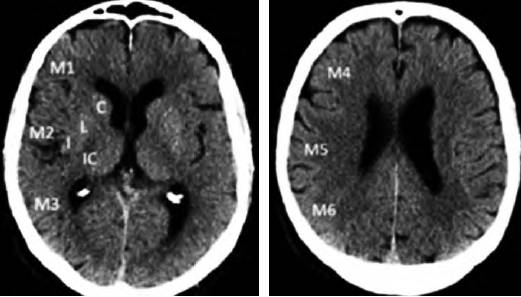

3.2.1 ASPECTS评分

ASPECTS评分是基于NCCT评估MCA区域早期缺血改变简单而系统的一种方法。将MCA供血区各主要功能区分别赋分(4个皮层下区:尾状核C、豆状核L、内囊IC、岛叶I;6个皮层区,标志为M1-M6)(图1),共计10 分,每累及一个区域减去1分,即正常脑CT为10分,MCA供血区广泛梗死则为0分。

图1 ASPECTS评分中大脑中动脉供血区功能分区注:皮层下区:C:尾状核(caudate);L:豆状核(lentiform);IC:内囊(internal capsule);I:岛叶(insular ribbon);皮层区:M1-M6。ASPECTS:Alberta卒中项目早期计算机断层扫描评分

为评估后循环梗死患者早期梗死情况,PUE T Z等建立了评估后循环的AIS预后早期CT评分(pc-ASPECTS)。pc-ASPECTS总分也是10分:双侧丘脑和小脑各1分,双侧大脑后动脉供血区各1分,中脑和脑桥为2分(图2)。

图2 pc-ASPECTS评分中后循环供血区功能分区注:pc-ASPECTS:后循环急性卒中预后早期计算机断层扫描评分